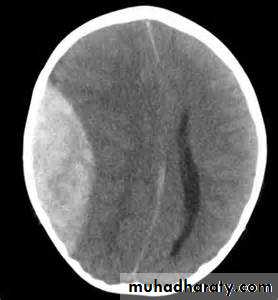

SUB DURAL

the principle imaging for ICH is CT scanning